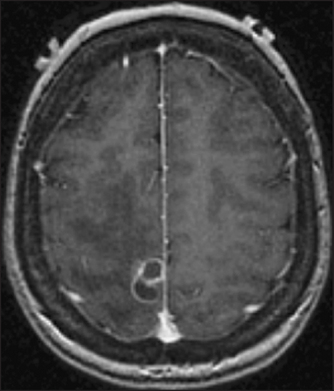

Figure 36.6 Brain abscess This gadolinium-enhanced MRI scan shows a multi-loculated ring-enhancing lesion caused by Nocardiainfection. (Goldman L. Goldman’s Cecil medicine, 24th edn. Saunders, 2011.)